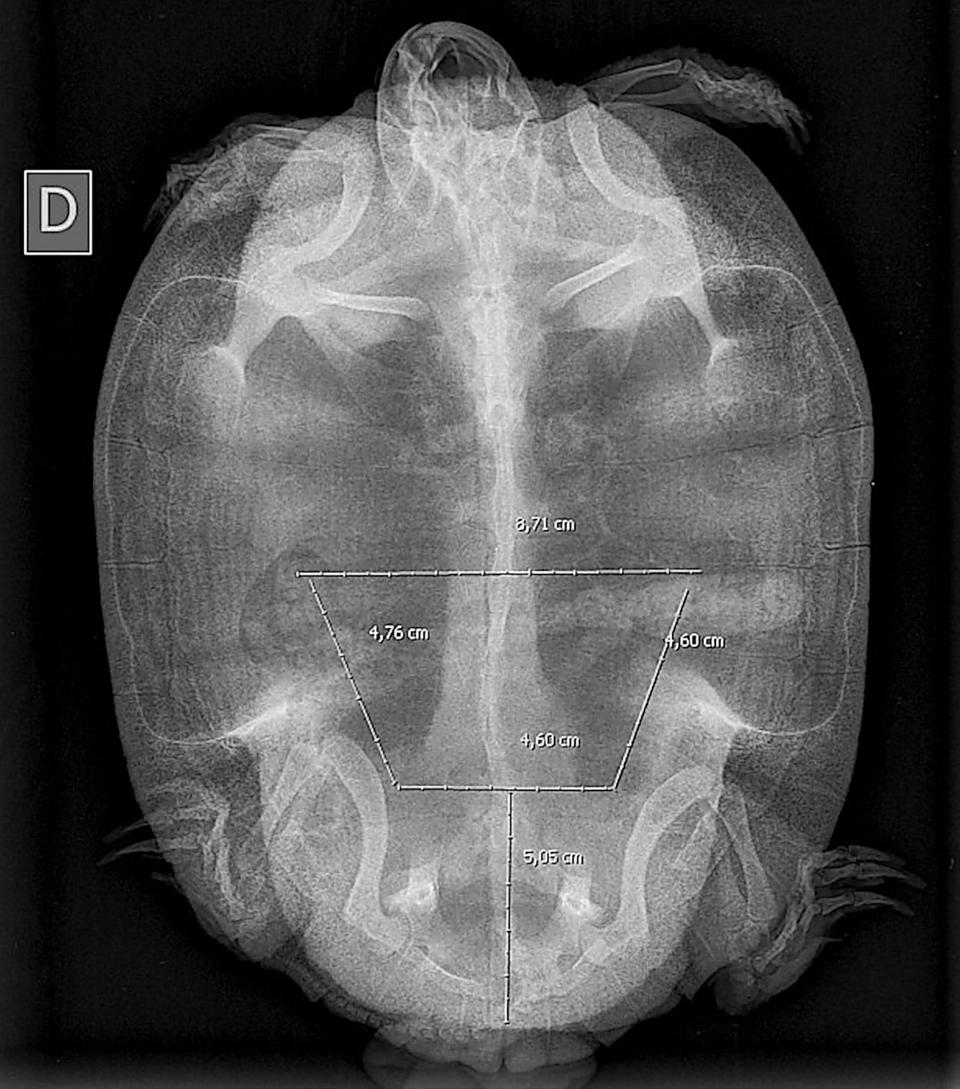

Dada la gravedad de la lesión se propone la realización de una celiotomía exploratoria. Para la planificación quirúrgica se obtiene una radiografía en la que no se detectan signos de obstrucción digestiva, distocia, ni otras anormalidades. Sobre la imagen radiológica se simula una ventana lo más caudal y amplia posible

Figura 3. Simulación de la osteotomía sobre imagen radiológica.